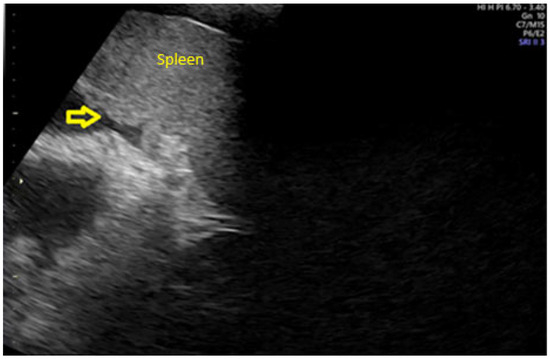

Background: Ovarian cancer is one of the most lethal gynecological malignancies, often diagnosed at an advanced stage. The prognosis is generally poor, with high recurrence rates and limited long-term survival. Understanding the genetic and molecular...